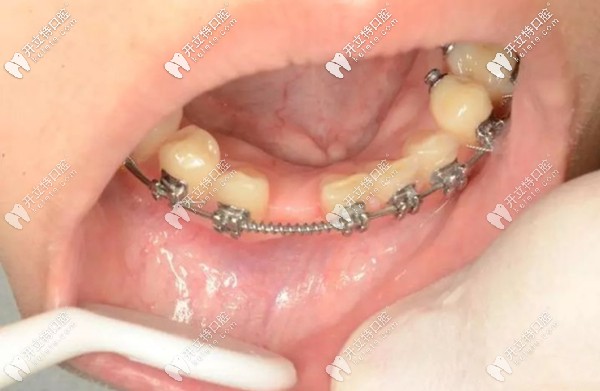

就例如,像我這種情況,下門牙先天缺失一顆,牙槽骨骨量充沛,在正畸進行到一半,也就是可以容納一顆種植體的時候,由種植醫(yī)生為我做了微創(chuàng)種植手術(shù)。

正畸過程中做種植牙的示意圖

看到?jīng)],缺牙部位已經(jīng)埋入了一顆種植體,而正畸的托槽和弓絲裝置還在牙齒上發(fā)揮這自己的作用。